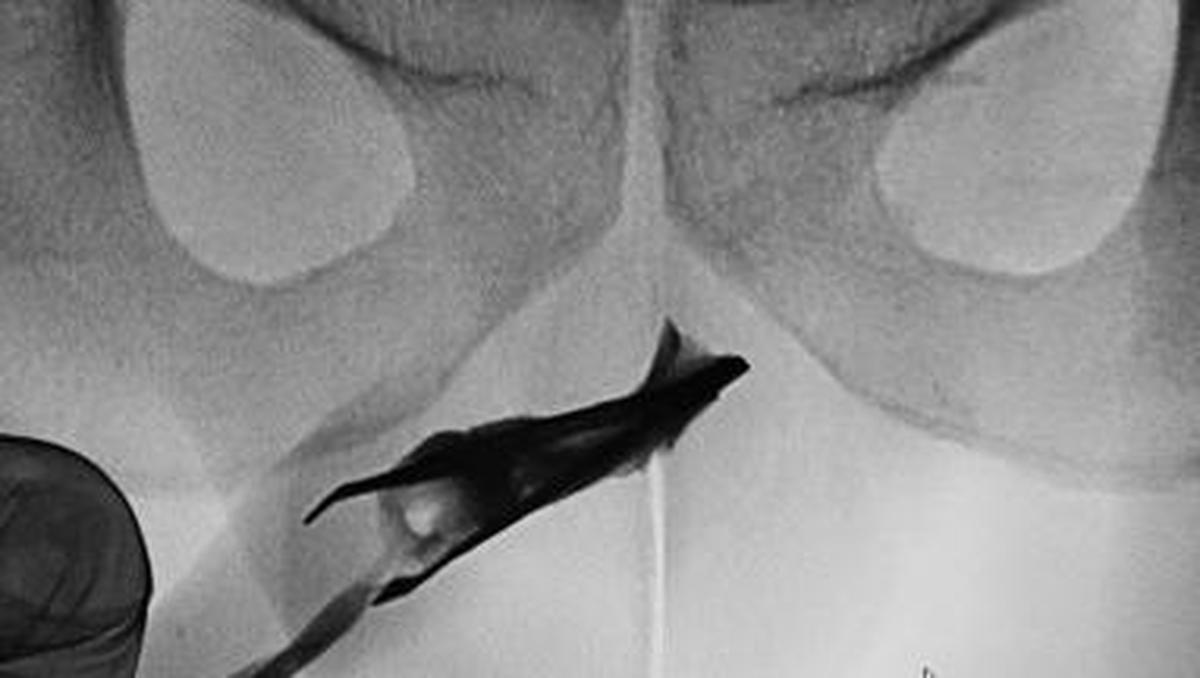

Jakarta – Seorang pasien pria berusia 22 tahun Hingga Arab Saudi datang Hingga Ahli Kebugaran Didalam pinset yang menyangkut Hingga penisnya. Benda itu ternyata sudah ada Di 4 tahun.